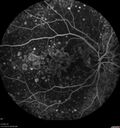

79 year old vision is in for a checkup with no visual complaints in the left eye. This is her better eye. VA 20/200 OD, 20/50 OS. 3 years ago she had a CRVO in the left eye. She is also diabetic for 20 years, has carotid insufficiency and anemia. Left eye shows CME. This was not treated and the vision improved to 20/40 over the next year although mild edema persisted.